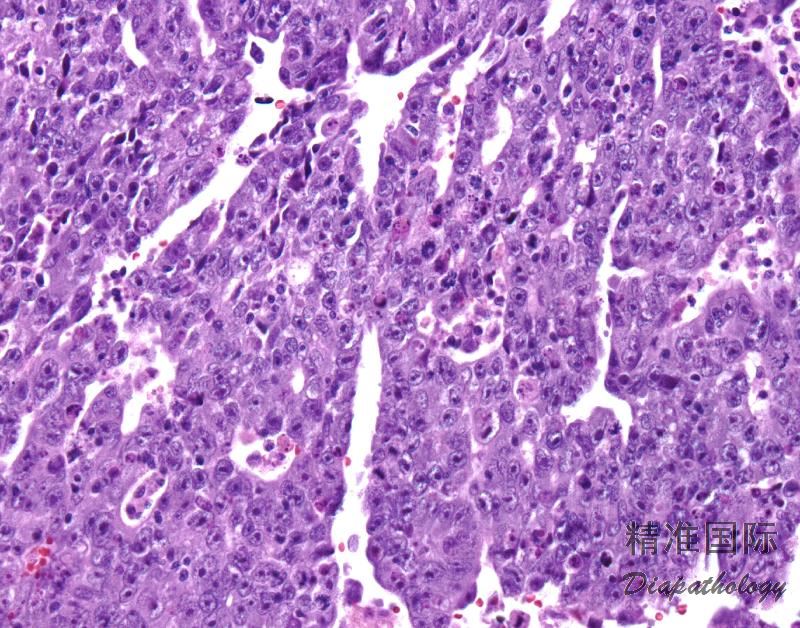

肿瘤细胞实性片状或巢状增生伴灶状腺样分化,在分化较好的肿瘤,除了形成实性区域外,瘤细胞还会衬覆裂隙和空腔,并形成乳头;

细胞中等到大,胞膜清楚,多边形或卵圆形,胞质丰富,淡染或嗜酸性颗粒状;细胞核大而明显,居中,空泡状或深染,有一定程度的不规则性。核膜清楚,一个或两个大的核仁。核分裂像和凋亡易见,异常核分裂像常见;

通常细胞多形性明显。可见巨细胞及多核细胞;

大多数病例可见合体滋养细胞;

局灶坏死、出血较常见。